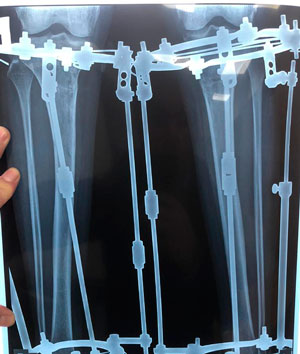

рентген перед фиксацией

IMG_6324-10-10-19-04-42.JPG

IMG_6323-10-10-19-04-42.JPG